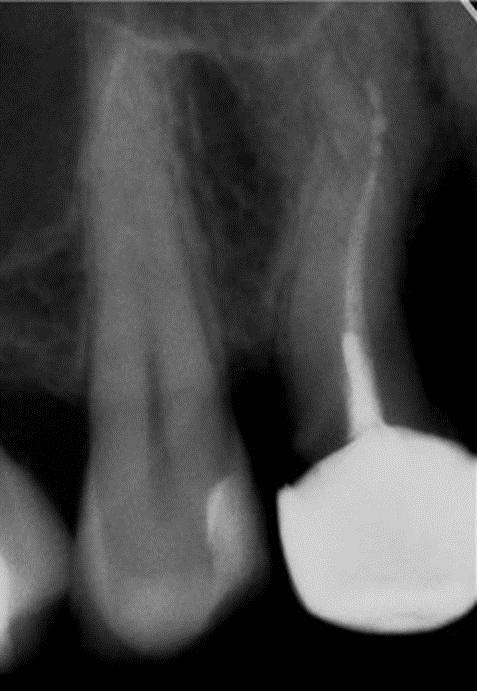

Проходження непрохідних каналів

• клініка

• діагностика

• менеджмент

Чи бувають непрохідні канали? Які ознаки прохідності? коли треба зупинитися і ухвалити рішення не йти далі. Механізм роботи зі ступенями із застосуванням мікроскопа і без, Механізм нівелювання сходинок. Фішки обтурації каналів при неможливості обійти або нівелювати сходинки.